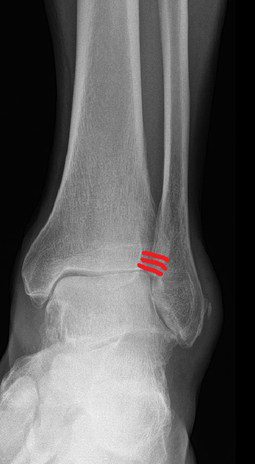

Bei frischen Verletzungen können meistens Bandanteile mit Fäden augmentiert und am Knochen wieder fixiert werden. Mitunter erfolgt die Fixierung des Bandes mittels im Knochen eingebrachter Ankersysteme, über die das Band angenäht werden kann. Um ein Ausreißen der Anker bzw Fäden verhindern zu können, werden üblicherweise „Stellschrauben", die das Wadenbein am Schienbein etwas oberhalb des Sprunggelenks fixieren, gesetzt.

Diese Schrauben müssen vor Beginn der Gehbelastung in aller Regel entfernt wieder werden. Alternativ kann ein sogenanntes Tight Rope, ein Kunstband, das über einen Bohrkanal das Schien- am Wadenbein fixiert, verwendet werden.